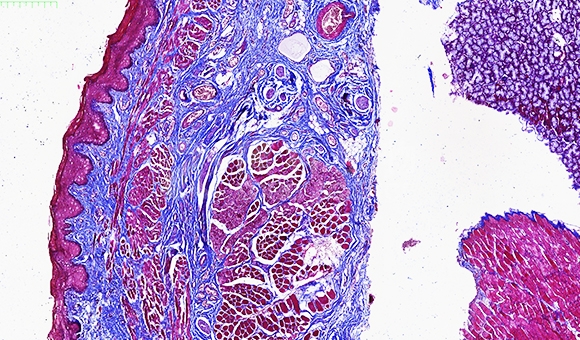

冰冻切片及染色

特殊染色

冰冻切片是一种在低温条件下使组织快速冷冻到一定的硬度,然后进行切片的一种方法。制作过程较石蜡切片快捷、简便,因而多应用于手术中的快